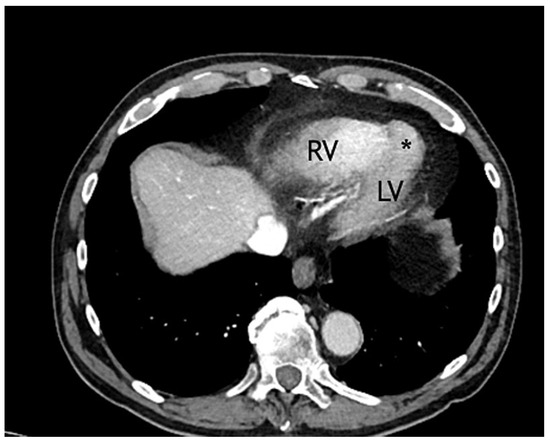

Congenital Left Ventricular Diverticulum in an Asymptomatic Patient: Multi-Modal Evaluation

by Negro Alessandro, Carballo David, Noble Stéphane and Müller Hajo

Congenital left ventricular diverticula are rare cardiac malformations. Few data are available regarding their prevalence, which is estimated to be around 0.04% and 0.7%, according to retrospective series. In our case a diverticular apical lesion of the left ventricle was incidentally found on [...] Read more.

Congenital left ventricular diverticula are rare cardiac malformations. Few data are available regarding their prevalence, which is estimated to be around 0.04% and 0.7%, according to retrospective series. In our case a diverticular apical lesion of the left ventricle was incidentally found on an urgent thoracic computed tomography scan, performed to rule out abdominal aortic rupture. A thorough evaluation with echocardiography, coronary angiography, ventriculography and cardiac magnetic resonance imaging was performed. After discussion in our heart team, which took into consideration the lack of cardiac symptoms, the small size of the diverticulum and the absence of thrombus, we decided on a conservative option. Full article